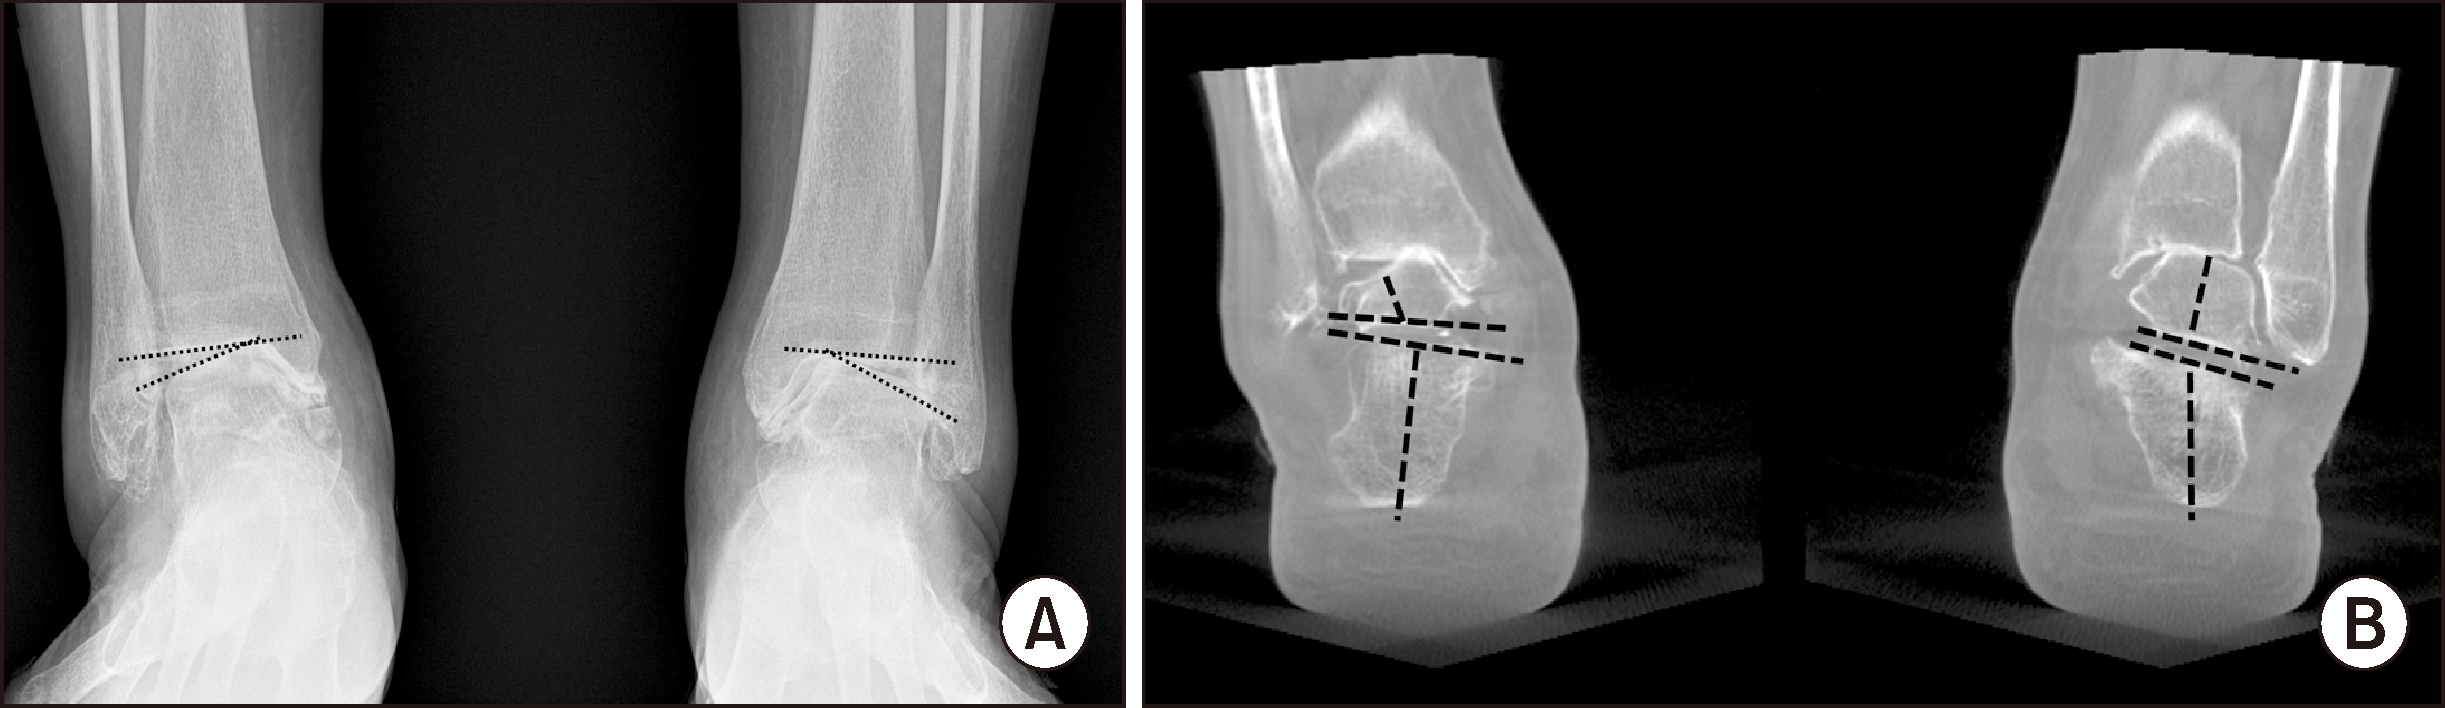

Figure 6

(A) Arthritis showing a difference in the talar tilt angle on standing radiographs of both sides. (B) The compensation of the subtalar joint on weight-bearing computed tomography is observed on the right side with a smaller talar tilt angle, but is not seen on the left side with a larger talar tilt angle.

Figure 7

(A) Preoperative weight-bearing computed tomography (WBCT) before supramalleolar osteotomy (SMO), (B) postoperative WBCT after SMO. These images reveal a significant correction of the abnormal internal rotation of the talus and recovered congruency of the ankle mortise in both the coronal (black arrow) and sagittal (white arrow) images.